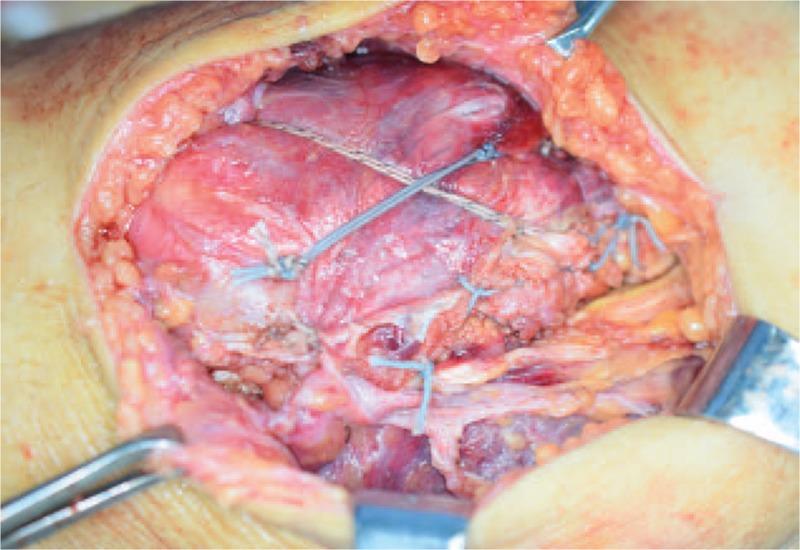

Under general anesthesia, the patient underwent open surgery for reduction of the patellar fracture and reconstruction of the knee extension apparatus through an anterior approach.

在全身麻醉下,患者通过前路接受开放手术,以复位髌骨骨折并重建膝关节伸展装置。